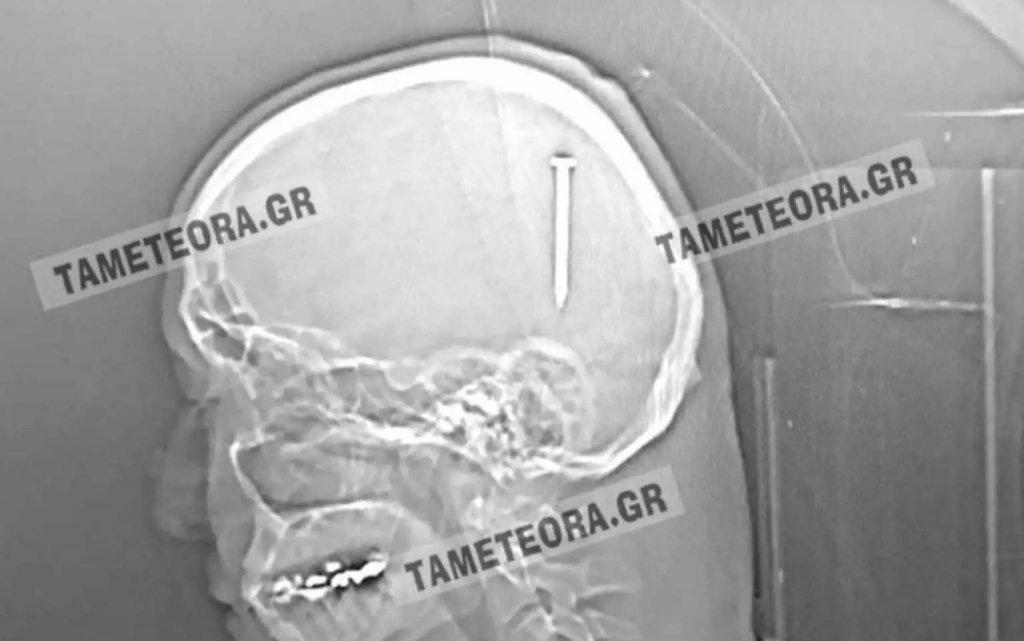

«Άγιο» είχε ένας άνδρας στη Καλαμπάκα, ο οποίος βρέθηκε ξαφνικά με ένα καρφί πέντε εκατοστών στο κεφάλι του.

Όλα συνέβησαν όταν ο πρωταγωνιστής της ιστορίας, κατά τη διάρκεια εργασιών, ένιωσε ένα τράνταγμα, χωρίς όμως πόνο ή κάποιο άλλο σύμπτωμα.

Αρχικά μεταφέρθηκε στο Κέντρο Υγείας Καλαμπάκας και στη συνέχεια στο Γενικό Νοσοκομείο Τρικάλων. Από εκεί «πήρε τον δρόμο» για το Πανεπιστημιακό Νοσοκομείο Λάρισας, όπου του έγινε επέμβαση και του αφαιρέθηκε το καρφί με επιτυχία.

Σύμφωνα με την ιστοσελίδα tameteora.gr, ο Καλαμπακιώτης αναρρώνει υπό παρακολούθηση, αλλά εκτιμάται ότι δεν διατρέχει κανέναν κίνδυνο η υγεία του. Πρόκειται πραγματικά για ένα σπανιότατο περιστατικό, καθώς αν το καρφί βρισκόταν ελάχιστα χιλιοστά από το σημείο που σφηνώθηκε, θα ήταν πολύ επικίνδυνο για την υγεία του τραυματία.